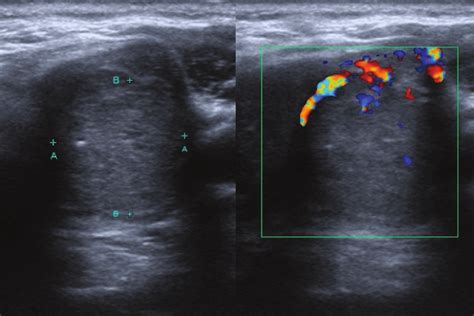

Mixed cystic and solid isoechoic thyroid nodule. .  <a href=https://cocktail-competition....Mixed cystic and solid isoechoic thyroid nodule. .  <a href=https://cocktail-competition....